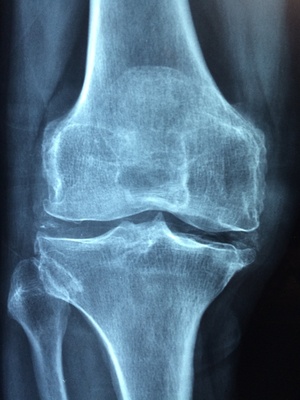

mp Groß-Gerau - Knochenaufbau und -abbau befinden sich nicht mehr in einem Gleichgewicht, sodass es schneller zu Frakturen kommen kann. Dr.Manuel Gonzales Reyes / pixabay.com

Dass die Knochendichte im Alter abnimmt, ist normal. Bereits ab dem 35. Lebensjahr schwindet sie jedes Jahr um etwa ein Prozent. Nimmt die Knochenmasse aber früher, schneller oder besonders stark ab, sprechen Mediziner von Osteoporose. Wörtlich übersetzt bedeutet das "löchriger Knochen". Knochenaufbau und -abbau befinden sich dann nicht mehr in einem Gleichgewicht, sodass es schneller zu Frakturen kommen kann.